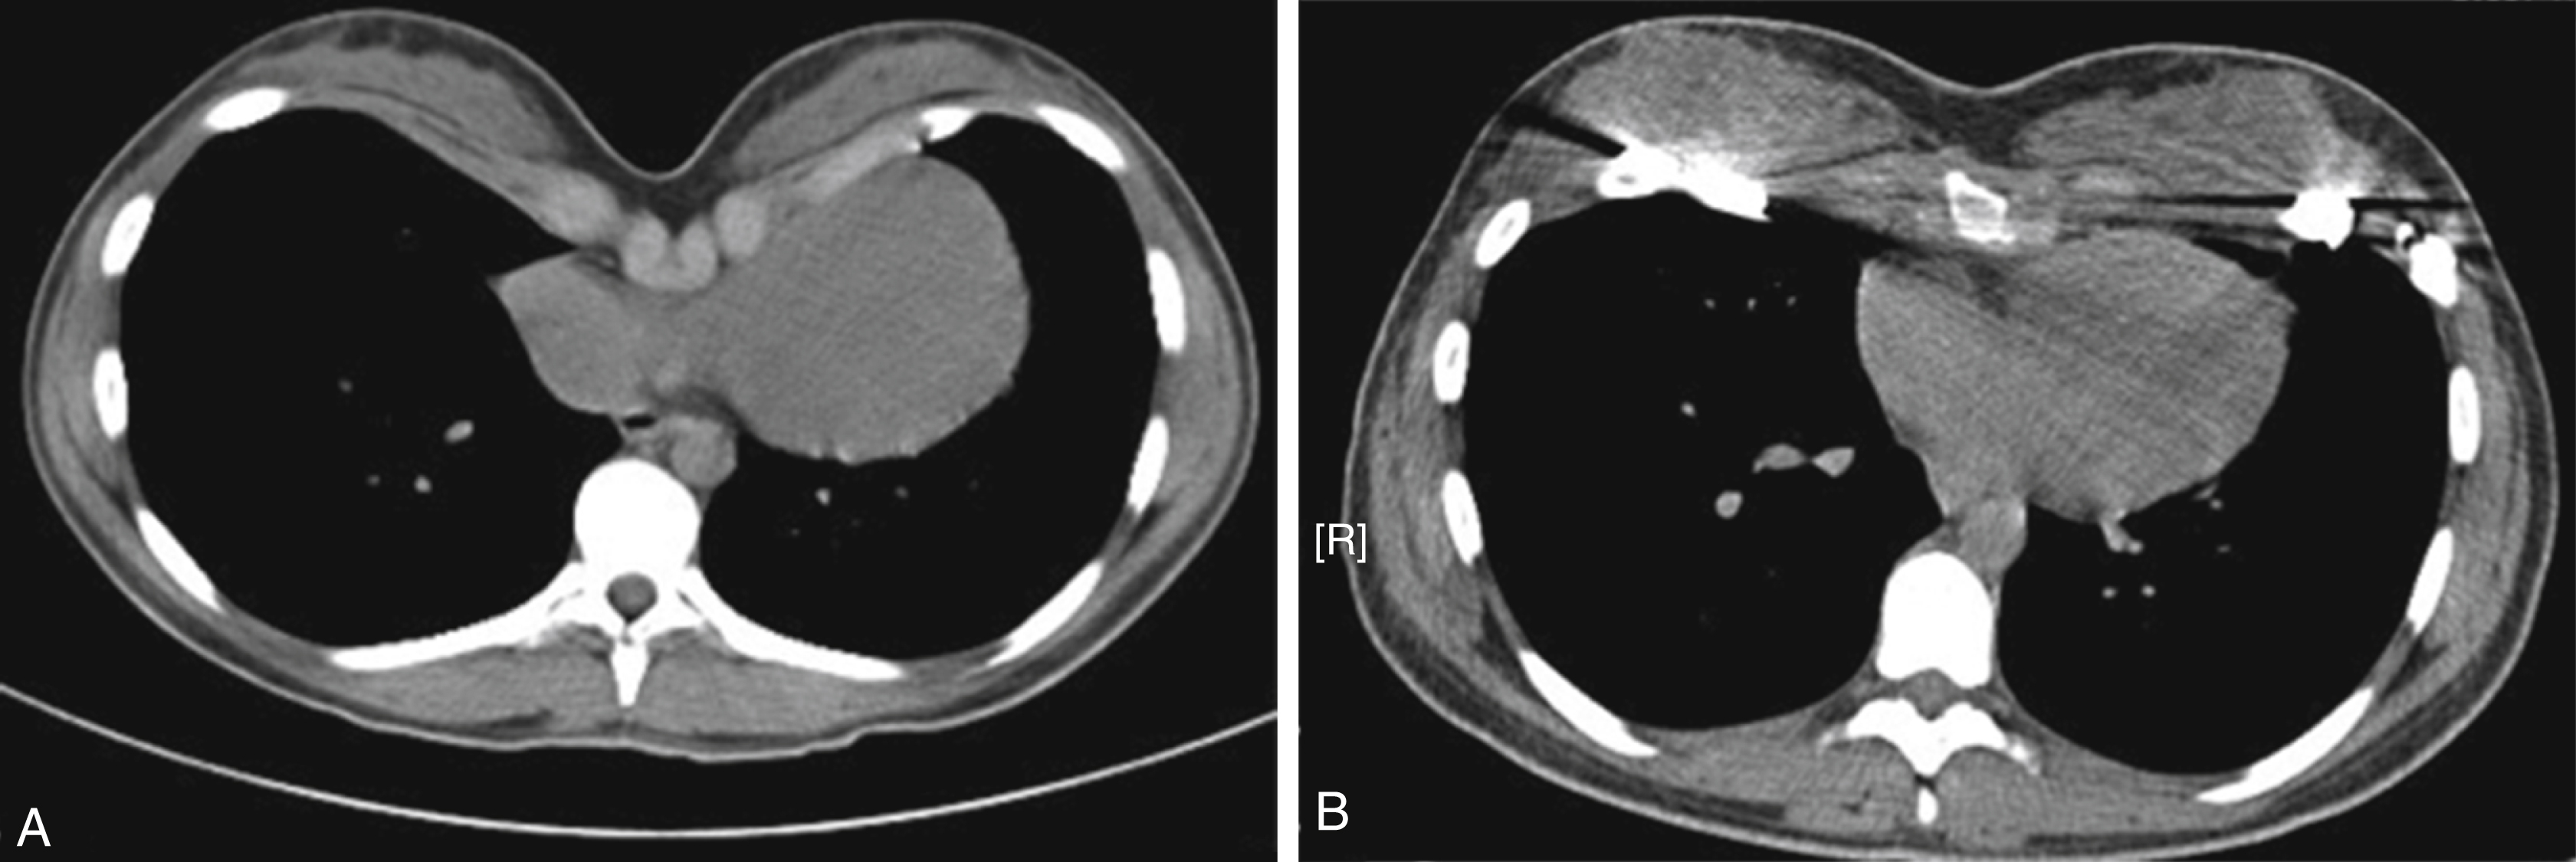

In this condition, there is a depression in the anterior of the chest wall of varying shape and severity ( Fig. 39.1 ).

Fig. 39.1

Transverse section of a computerized tomography (CT) scan of a patient with pectus excavatum, (A) before and (B) after Nuss correction. Note the cardiac compression seen before correction.

This is followed by computerized tomography (CT scan) imaging, which can be used to construct the 3D anatomy of the thoracic cavity. The Haller index of severity can be calculated from this. This is the ratio of the transverse diameter and the anteroposterior diameter of the rib cage. A normal ratio is 2.5. Of special importance is the shape and axis of the body of the sternum. Sternal torsion and asymmetry have an impact on the type of surgery. CT scan can also show associated anomalies including spinal deformities and also the extent of cardiac compression.